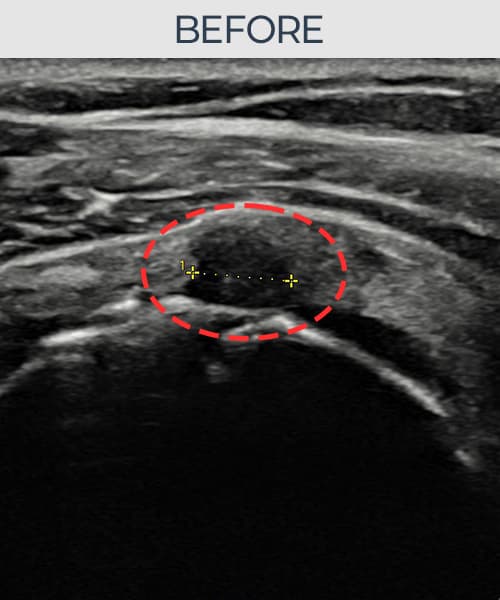

超音波検査にて腱板 部分断裂(6mm × 3mm (腱厚の約35%欠損))を確認。縫縮術施行後、腱の連続性が回復し、日常生活に復帰されました。

施術前

術前超音波にて腱板 部分断裂・肩棘上筋腱のエコー不連続と腱欠損(6mm × 3mm (腱厚の約35%欠損))を確認。術後超音波では断裂部位が再生組織で充填され、腱の連続性回復とエコーパターンの正常化が確認されました。

持続する肩痛で来院された患者様です。超音波検査にて腱板 部分断裂(欠損:6mm × 3mm (腱厚の約35%欠損))を確認し、超音波ガイド下で非手術的縫縮術を施行しました。術後は約4〜6週間のブレース装着の後、段階的なリハビリプログラムを実施。経過超音波で腱の連続性回復を確認し、患者様は無事に日常生活へ復帰されました。